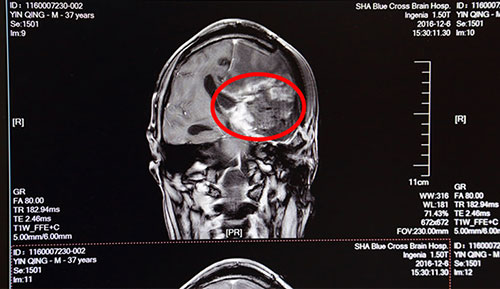

术前影像资料:红圈内为肿瘤物

患者殷某,男,37岁,于2016年04月因胶质瘤复发,行粒子置入术,后出现神志不清伴右侧肢体障碍。在这之前,患者已做过几次肿瘤切除手术及放射性治疗,2011年7月28日在上海某医院第一次行胶质瘤切除术,2015年6月胶质瘤复发第二次行手术切除,期间有过两次化疗,6月复查头颅CT示:胶质瘤较前增大。为进一步治疗,2016年12月6日来到蓝十字脑科医院,门诊以“胶质瘤术后复发”收入神经外科,主诉神志不清伴右侧肢体活动障碍8月余。

蓝十字脑科医院神经外科侯增欣主任等针对患者病情进行了联合会诊讨论。根据患者病史及影像学资料,肿物位于左侧额颞叶,占位效应及高颅压症状明显。患者目前具有手术指征,需尽早手术治疗,术中应尽量切除肿瘤,缓解颅内压,明确诊断,否则恐危及生命。又鉴于患者多次手术,且肿瘤血供丰富,术中可能大出血,术后可能出现肢体瘫痪加重且永久、偏身感觉障碍及颅内迟发性出血、血肿或其他部位出血(如脑室内出血)等,危及生命可能。此外,患者此前做过粒子植入术,粒子为高放射物,相关机构对粒子的管控极其严格,不仅需要申请资质,而且每一枚粒子的出入都经过严格备案,一般医院是没有粒子相关处理经验的,因此对手术如何处理病人颅脑中植入的粒子也是极其棘手的问题。由此可见手术难度之大,将十分考验主刀医生,实为不小的挑战。